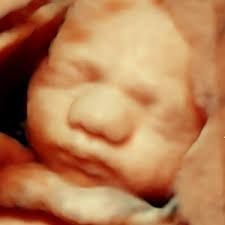

3D/4D echo van je eigen kindje is een hele bijzondere ervaring. Tussen 25 en 30 weken is de ideale periode voor de mooiste beelden. Het kindje krijgt vanaf 25 weken al meer contouren waardoor het gezicht beter herkenbaar worden. Vanaf 30 weken is de kans wat groter dat het kindje diep in het bekken gaat liggen en het daardoor minder goed zichtbaar is.

Lukt het niet om het kindje in 3D beeld te krijgen, dan mag je gratis nog een keer terug komen.

Deze echo kost € 70,-